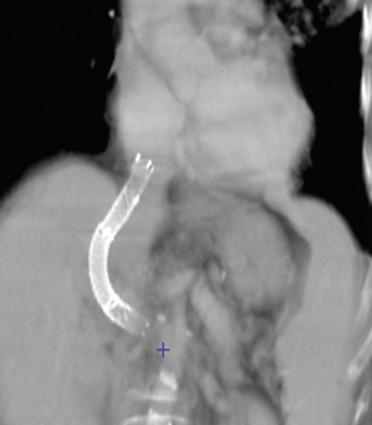

Figura 1. La rimozione del fegato nativo viene eseguita preservando la continuità della vena cava inferiore. Viene praticata temporaneamente un’anastomosi portocavale terminolaterale per preservare, durante la fase anepatica, il drenaggio venoso del territorio splancnico. 1. Vena cava inferiore; 2. anastomosi portocavale.

La conservazione della continuità della vena cava inferiore durante la rimozione del fegato malato e la creazione di un’anastomosi portocavale temporanea (durante la fase anepatica) sono i modi più semplici ed efficaci di evitare queste complicanze [10] (Fig. 1). È divenuto inoltre eccezionale il ricorso all’impianto di uno shunt extracorporeo venovenoso tra la vena porta e la vena cava inferiore (VCI) (attraverso la vena iliaca esterna) da un lato e la vena cava superiore (tramite la vena ascellare) dall’altro (Fig. 2). Una volta installato, lo shunt utilizzato dalla maggior parte delle equipe è uno shunt “attivo”, con il sangue propulso tramite una pompa. L’uso proposto da Shaw et al. [11] della pompa non occlusiva, operante per effetto Venturi (Biomedicus® ) e associata a un circuito “rivestito” di eparina, evita l’anticoagulazione del ricevente per via sistemica.

Figura 9. Campo operatorio durante la fase anepatica. Il flusso della vena cava e il flusso splancnico sono rispettivamente preservati dalla conservazione della vena cava inferiore retroepatica e dalla creazione di un’anastomosi portocavale temporanea.